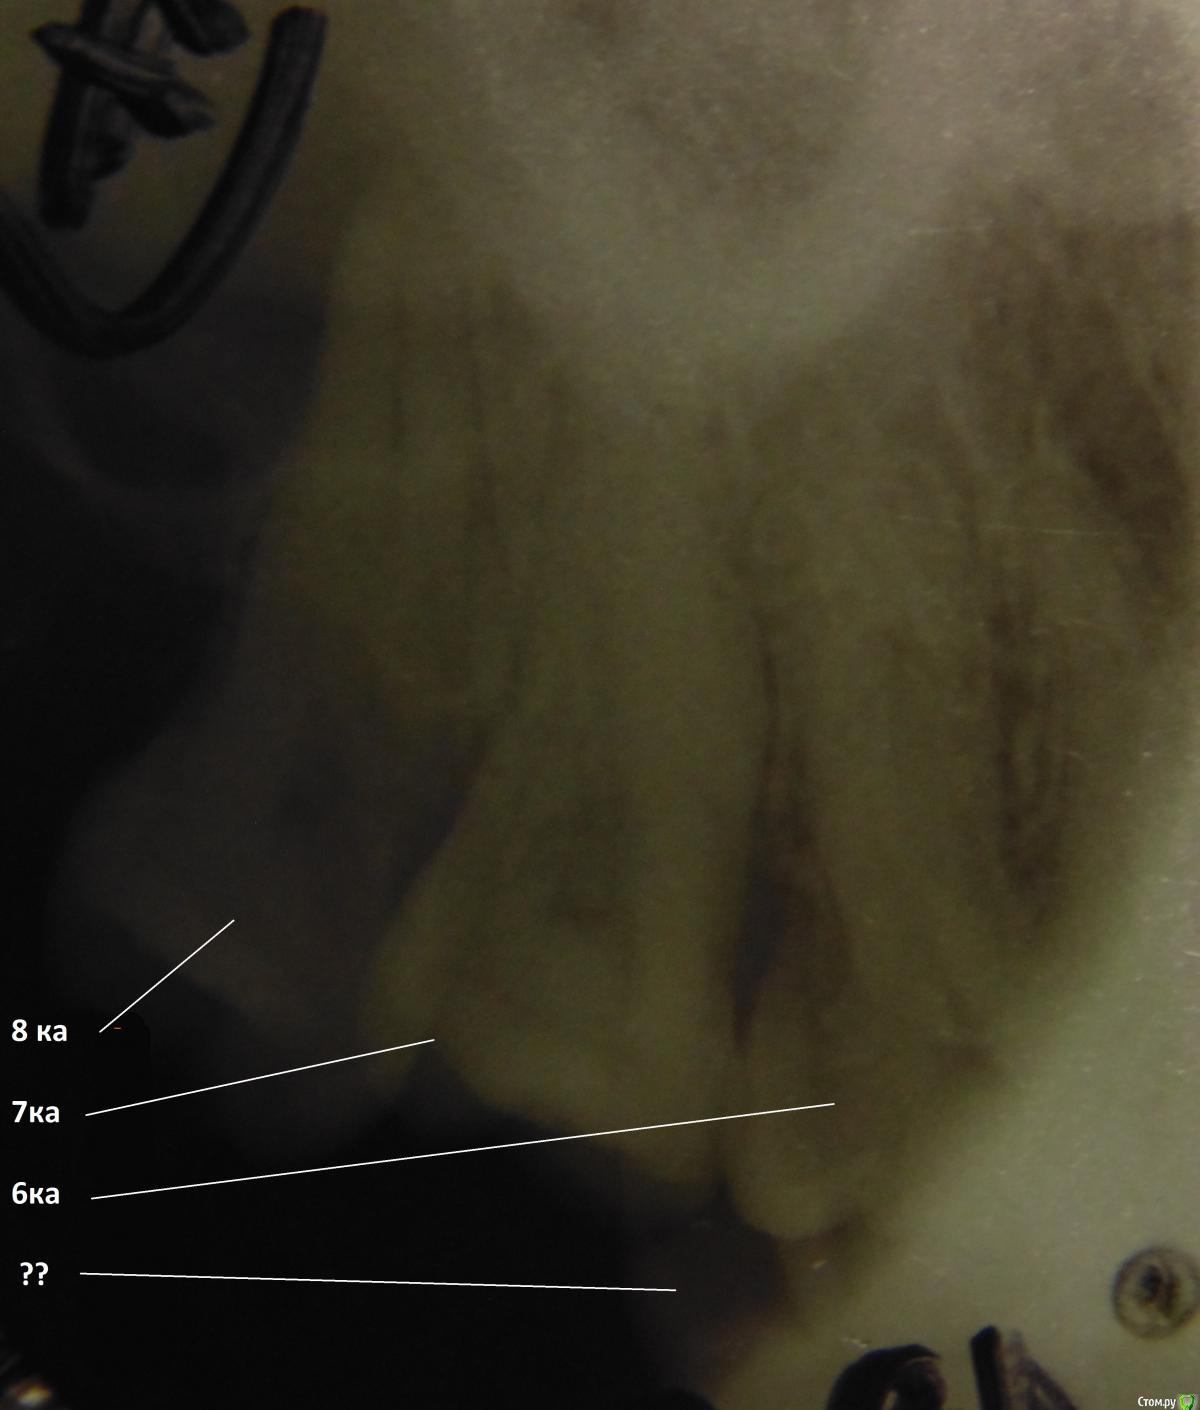

___49___ Опубликовано 18 марта, 2016 Автор Поделиться Опубликовано 18 марта, 2016 29ка ..... нет наверное S 26.5 Ссылка на комментарий